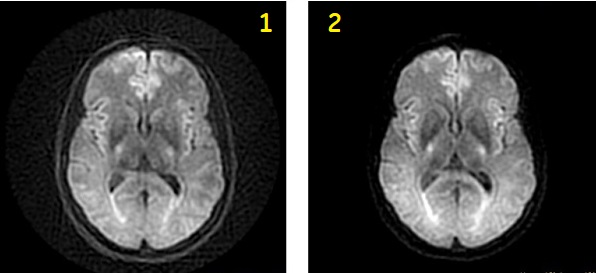

| Number | Description |

|---|---|

| 1 | EPI DWI |

| 2 | DW PROPELLER |